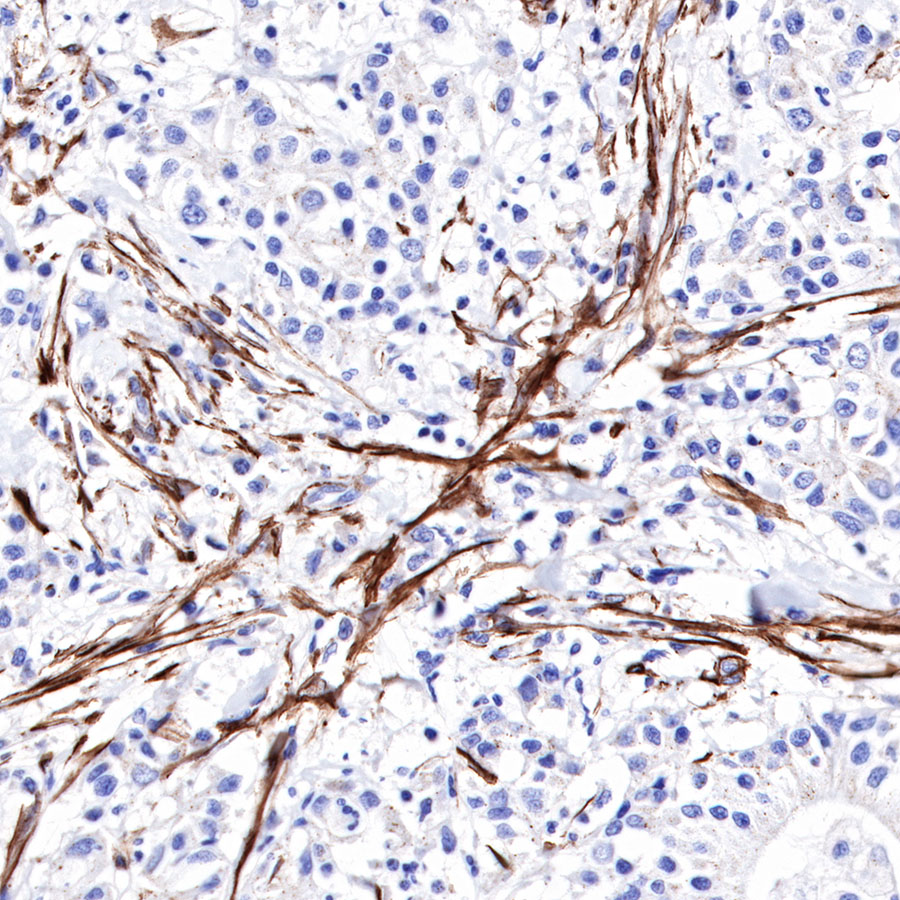

Immunohistochemistry